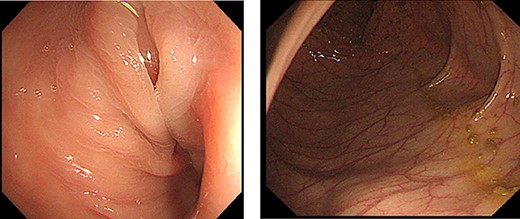

Endoscopic examination showed that the site of torsion was near the sigmoid rectum (Fig. 1), and a computed tomography(CT) scan revealed prominent dilatation of the oral bowel (Fig. 2).

Colonoscopy findings. Torsion was observed in sigmoid rectum. No mucosal necrosis was observed.